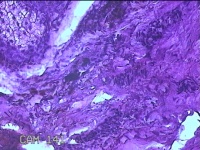

右侧颜面部黑痣

性别

男

年龄

41岁

临床诊断

耳后脓肿:痣

一般病史

发现右侧颜面部黑痣多年,无疼痛及不适。

标本名称

大体所见

灰白暗红色肿物0.8x0.5x0.3cm两个,表面糜烂,切开肿物呈实性,切面灰白暗红色,质软。